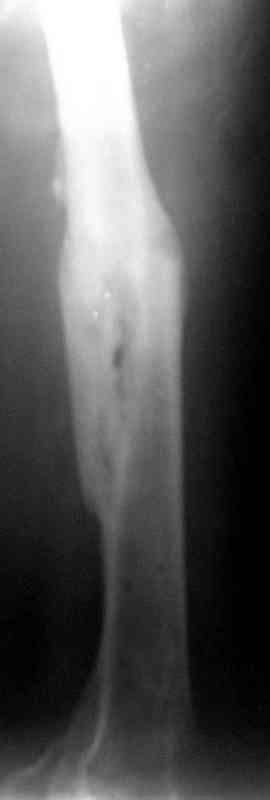

Уважаемые коллеги!На прилагаемых снимках - состояние после оперативного вмешательства (открытый перелом левого бедра в средней трети):

МОС, стержень нефиксированный. С момента операции прошло 8 месКак по Вашему мнению происходит консолидация? Допустимо ли смещение или необходима повторная операция по выравниванию конечности? Если да, какой метод рекомендуете (фиксированный стержень, пластина)?Буду благодарен за оперативный ответ.

Вы не пишете, есть ли сейчас болезненные проявления, и какие. Как пациент ходит. Какова функция колена. Ось выглядит приемлемо. Рентгенологически на сращение непохоже. Если есть клиника несращения (боль, хромота), то лучший выбор - закрыто рассверлить и перештифтовать блокированным гвоздем. Желательно определиться поточнее, нет ли проблемы с длиной , чтобы попутно и ее решить. И не создать. Ну и прежде всего исключить инфекцию. Если это инфицицированное несращение, план надо другой.

Как по Вашему мнению происходит консолидация?

По-моему - замедлнно.

Допустимо ли смещение...

В этой проекции угловое смещение градусов 15-20 - многовато будет. Есть ли укорочение?